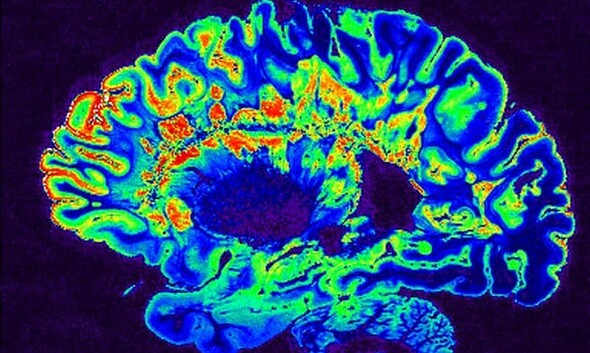

Un medicament numit Metformină, care este prescris în mod frecvent pentru a trata diabetul, ar putea opri evoluția sclerozei multiple și chiar să repare nervii distruși,...